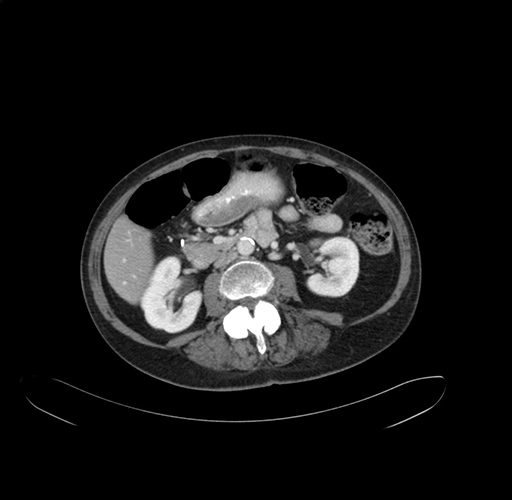

Axial Venous